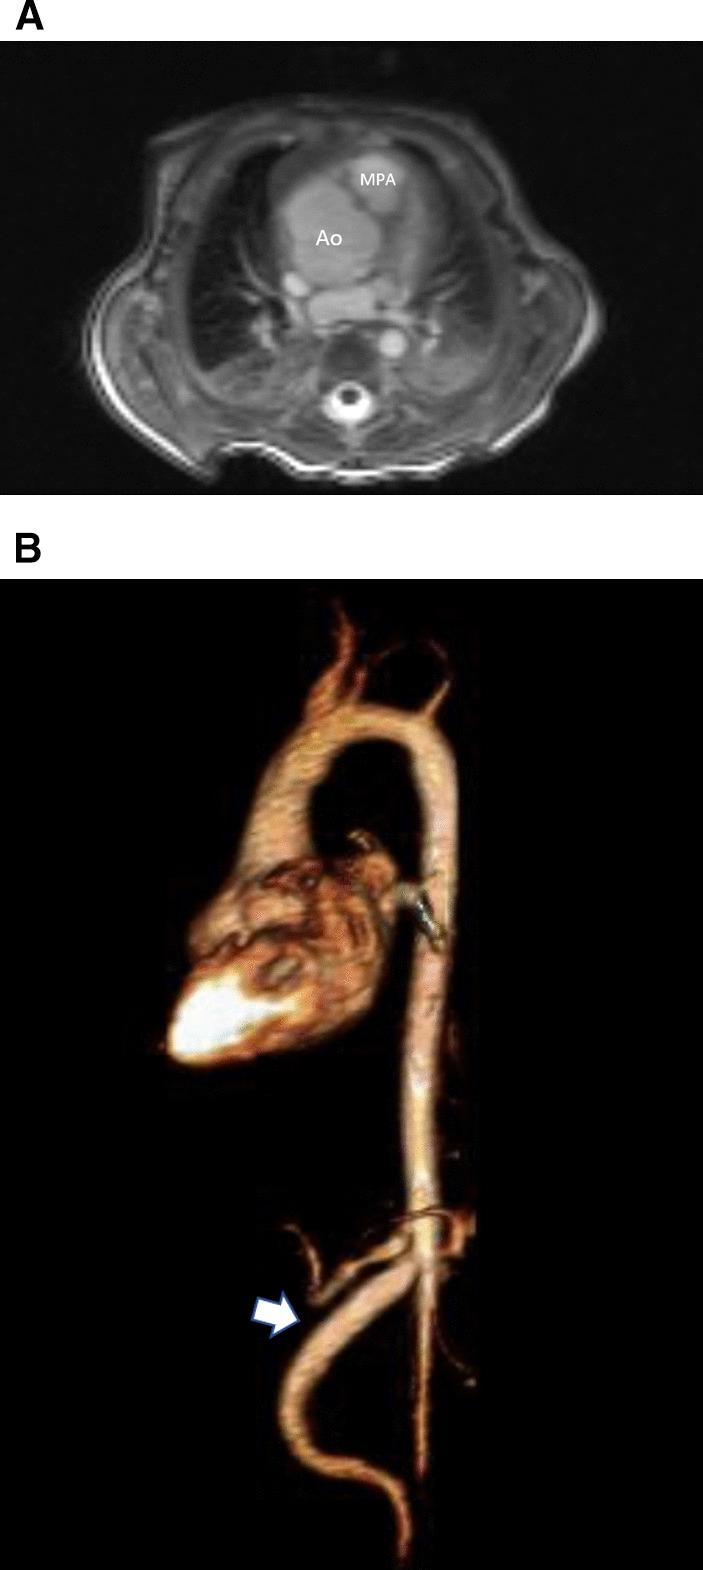

Cardiovascular magnetic resonance (CMR) has been utilized in the management and care of pediatric patients for nearly 40 years. It has evolved to become an invaluable tool in the assessment of the littlest of hearts for diagnosis, pre-interventional management and follow-up care. Although mentioned in a number of consensus and guidelines documents, an up-to-date, large, stand-alone guidance work for the use of CMR in pediatric congenital 36 and acquired 35 heart disease endorsed by numerous Societies involved in the care of these children is lacking. This guidelines document outlines the use of CMR in this patient population for a significant number of heart lesions in this age group and although admittedly, is not an exhaustive treatment, it does deal with an expansive list of many common clinical issues encountered in daily practice.

心血管磁共振(CMR)在儿科患者的管理和护理中已经应用了近 40 年。它已经发展成为评估最小的心脏的宝贵工具,用于诊断、介入前管理和随访。尽管在许多共识和指南文件中提到,但在儿科先天性心脏病和后天性心脏病领域,目前还缺乏一份由众多参与儿童护理的学会共同认可的、最新的、独立的、针对 CMR 使用的大型指南。本指南文件概述了 CMR 在该年龄段的许多心脏病变中的应用,尽管不能说是详尽的治疗方法,但它确实涉及了在日常实践中经常遇到的许多常见临床问题的广泛列表。